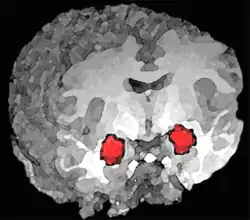

• Amígdala cerebral. Algunos estudios basados en diversas técnicas de exploración por imágenes muestran que los mecanismos cerebrales subyacentes a la impulsividad, inestabilidad emocional, agresividad, ira y emociones negativas podrían estar en una desregulación de los circuitos neuronales que modulan las emociones. En especial, se han observado pequeñas diferencias individuales en como se regula la amígdala, un núcleo cerebral que desencadena el pánico o la ira en respuesta a estímulos de peligro procedentes de otras áreas cerebrales. Algunos individuos tienen dificultades para inhibir esta respuesta desde el área prefrontal. Se sabe que el abuso de substancias o el estrés empeoran esta capacidad de inhibición.[25][26]​ En 2003 se realizó un estudio sobre afectados de TLP, viendo que mostraban una actividad significativamente superior en la amígdala izquierda, en comparación con sujetos normales. Algunos pacientes con este trastorno incluso tenían dificultades para clasificar caras neutras, que veían como amenazantes.[27]

Posición de la amígdala en el cerebro humano. Es una reconstrucción tridimensonal de una imagen por resonancia magnética funcional (fRMN) en el que se ve la amígdala activada.